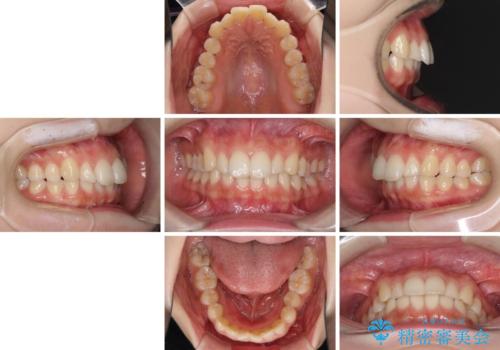

インビザラインを断念 ワイヤー装置で楽々と矯正治療

- 上の前歯が出っ張っている気がするとのことで来院された患者様です。

急いで治す必要性がないとのことで、自分のペースでのんびりと治療を行えるインビザラインにて矯正治療を行うこととしました。

半年もせずにインビザラインを全く使用することができなくなってしまったので、治療開始から1年ほどでワイヤー矯正へ変更することとなりました。

ワイヤー矯正へ変更してからはあっという間に治療が進み、1年弱で終えることができました。